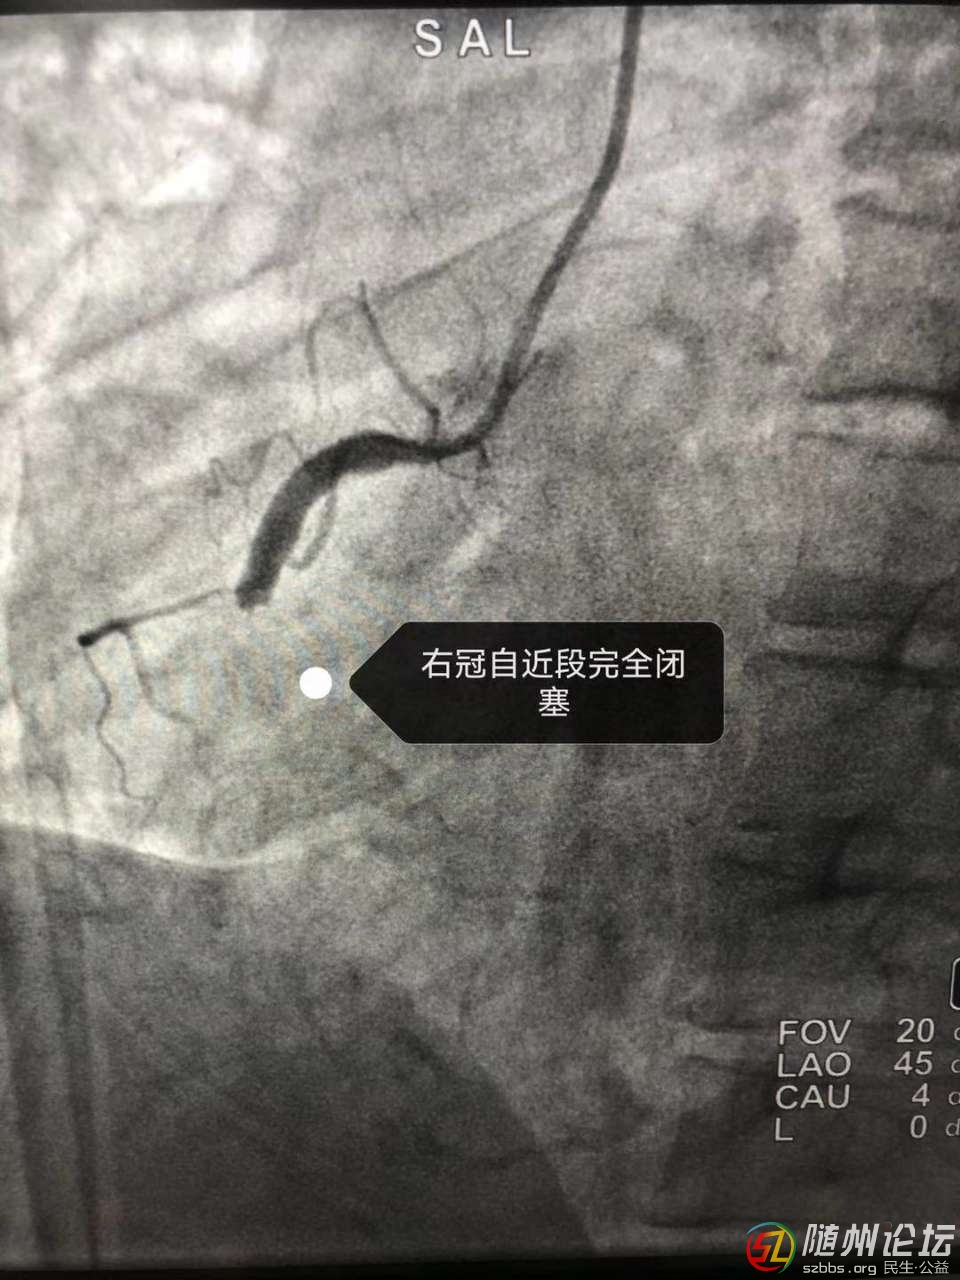

近日,隨縣中醫(yī)醫(yī)院上演了一場“生死時速”,成功救治1例急性心肌梗死患者,患者黃女士,46歲,在上班途中突發(fā)胸痛、胸悶、失語、持續(xù)不緩解,周圍人員撥打120后急診科出診,經(jīng)評估患者胸痛、失語、血壓80/50mmHg,心電圖顯示急性下壁ST段抬高性心肌梗死,患者病情危重,隨時有猝死風(fēng)險,經(jīng)心內(nèi)科許山水主任評估后建議立即行冠狀動脈造影及經(jīng)皮冠狀動脈介入術(shù)(PCI),經(jīng)溝通后家屬同意手術(shù),遂立即啟動介入導(dǎo)管室,患者在40分鐘內(nèi)發(fā)生3次室顫,護士長行3次電除顫后患者心電血壓不穩(wěn)定,先后給予利多卡因、去甲腎上腺素等藥物治療,待心率稍穩(wěn)定,繼續(xù)行冠狀動脈造影,術(shù)中造影顯示右冠近端完全閉塞,在上級醫(yī)師丁紅教授的指導(dǎo)下,許山水主任獨立完成球囊擴張(PTCA)、支架植入、冠脈內(nèi)溶栓和血栓抽吸術(shù),再次造影后,支架貼壁良好,血流恢復(fù)通暢,患者轉(zhuǎn)危為安,安全下臺,患者得到了及時、有效的救治。急性心肌梗死病情重,死亡率高,合并室顫更容易導(dǎo)致患者猝死,時間就是心肌,時間就是生命!